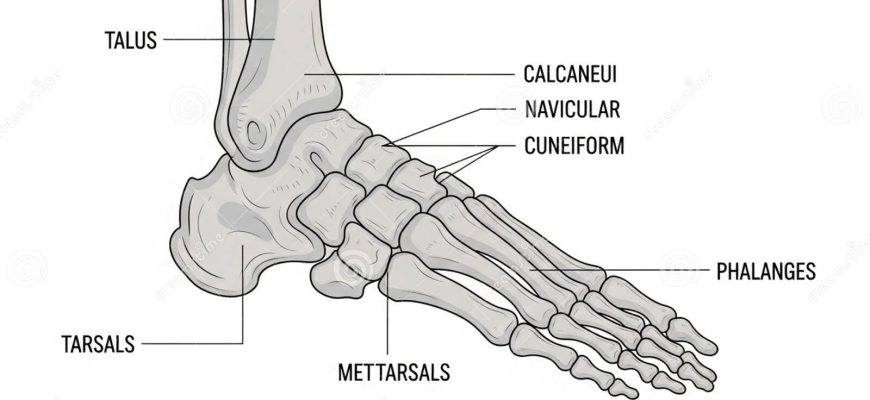

Анатомия таранной кости: секреты строения и функции этой важнейшей части стопы Когда мы говорим о нашей способности двигаться, удерживать равновесие и

Анатомия таранной кости: ключ к пониманию строения стопы и ее функции Когда мы задумываемся о здоровье нашей стопы, зачастую вспоминаем о костях, мышцах

Анатомия таранной кости: ключ к пониманию строения и функций стопы Когда мы задумываемся о здоровье наших стоп, особенно о таких сложных и важных структурах

Анатомия таранной кости: ключ к пониманию стопы и её функций Когда мы говорим о здоровье и функциональности человеческой стопы, одна из самых важных составляющих

Анатомия таранной кости: ключ к пониманию анатомии стопы и ее функций Когда мы задумываемся о здоровье наших ног, особенно о таких сложных структурах

Анатомия Таранной Кости: Всё, что Нужно Знать о Незаменимом Элементе Стопы Когда мы задумываемся о здоровье наших ног, обычно обращаем внимание на такие

Анатомия суставных поверхностей таранной кости: все, что нужно знать о структуре и функциях Когда речь заходит о строении стопы и её двигательной функции